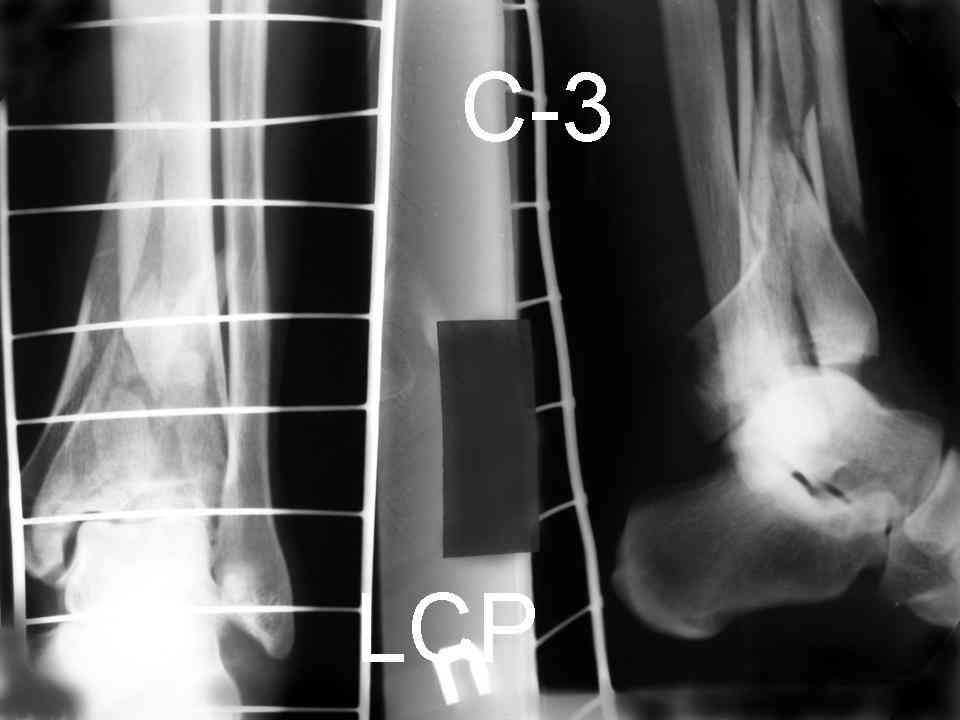

Дрягин В. 04 Январь 2007, 13:28

Кстати, при переломах переднего края по классификации АО В-3 при переломах пилона пластина укладывается по передней поверхности. Она достаточно тонкая и эластичная, не надо этого бояться. Посылаю три снимка.